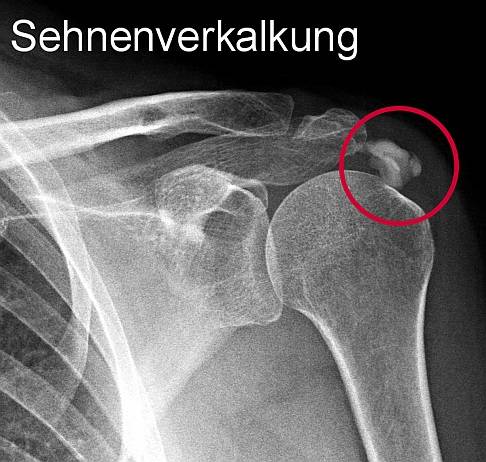

Kalkschulter

Wenn die Schulter auch nachts schmerzt und Sie nicht auf der Seite liegen können, leiden Sie möglicherweise an einer Kalkschulter. Die Kalkschulter führt zu schmerzhaften Bewegungseinschränkungen der Schulter. Mit Kalkschulter können Sie den betroffenen Arm nicht über Schulterhöhe oder über den Kopf heben.

Röntgenuntersuchungen zeigen zum Beispiel schmerzhafte Kalkeinlagerungen im Schultergelenk. © Gelenk-Klinik

Die Röntgenuntersuchung erlaubt die Untersuchung des Skeletts. Das Röntgen zeigt auch Kalkeinlagerungen ins Gewebe, eine häufige Ursache von Schulterschmerzen.